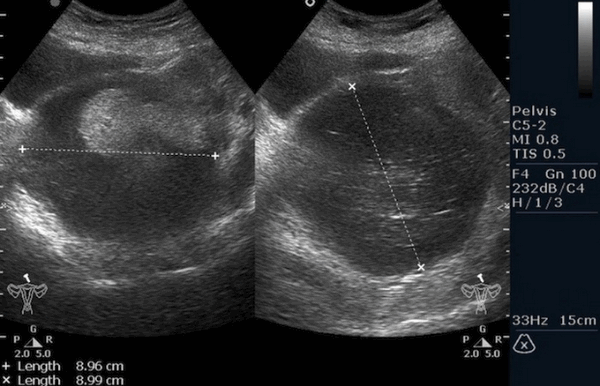

Ультразвуковое исследование (УЗИ) мошонки является предпочтительным начальным визуализирующим исследованием для оценки образования яичка. УЗИ может подтвердить наличие новообразования, определить его расположение и оценить состояние противоположного яичка (рис. 4). Чувствительность метода достаточно высокая – от 92 % до 98 %.

![Снимок УЗИ яичка]()

Снимок УЗИ яичка